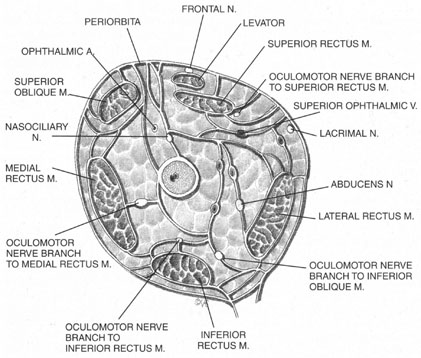

The ciliary ganglion is an irregular structure, measuring 1 mm by 2 mm, that lies just temporal to the optic nerve (Figs. 3 and 4), 7 to 10 mm from the orbital apex.47,51 In it the presynaptic parasympathetic fibers from the Edinger-Westphal nucleus synapse with the postsynaptic fibers that form the short ciliary nerves. Most of these fibers innervate the ciliary muscle, and the remaining 3% to 5% supply the iris sphincter. The ganglion also contains sensory branches of the nasociliary nerve and sympathetic fibers en route to the choroidal vasculature.

Blocks delivered in the anterior or middle orbit depend on diffusion of the anesthetic agent into either the posterior orbit, to the origin of the nerve branches, or into the muscles themselves at the point where distal branches insert into myoneural junctions. The first process is dependent on the anatomy of the connective tissue planes that subdivide the orbit into compartments (see Fig. 4). This architecture varies among patients. The classic teaching of a single intermuscular septum that connects the rectus muscles and divides the orbit into an intraconal and an extraconal space is overly simplified. Histologic examination of the orbit reveals an arrangement of roughly parallel and partially broken septa of various thicknesses, with and without fenestrations.48 This anatomic variability, therefore, accounts for the variability in akinesia seen with orbital blocks.

Because permanent extraocular muscle damage is more a product of intramuscular or intraneural injection than of the concentration of anesthetic injected,48,55 a less traumatic delivery of anesthetic can be used around the extraocular muscles to achieve akinesia without risking either myotoxicity or needle trauma to the adjacent optic nerve and orbital vessels. Using the sub-Tenon's space for this delivery allows for such atraumatic akinesia.